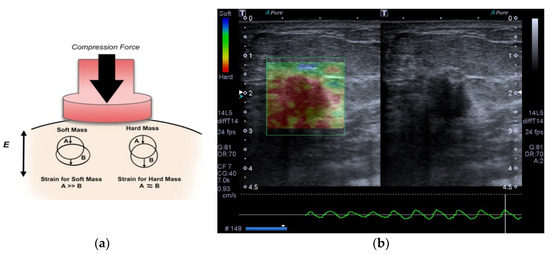

- Ophir, J. Elastography: A quantitative method for imaging the elasticity of biological tissues. Ultrason. Imaging 1991, 13, 111–134. [Google Scholar] [CrossRef] [PubMed]

- Hall, T. In vivo real-time freehand palpation imaging. Ultrasound Med. Biol. 2003, 29, 427–435. [Google Scholar] [CrossRef]

- Diaz, J.J.; Castellanos, N.P.; Pineda, C.; Hernandez, C.; Ventura, L.; Gutierrez, J. Algorithm to estimate the level of elasticity of biological tissue with ultrasound elastography images. In Proceedings of the 2015 Pan American Health Care Exchanges (PAHCE), Vina del Mar, Chile, 23–28 March 2015. [Google Scholar] [CrossRef]